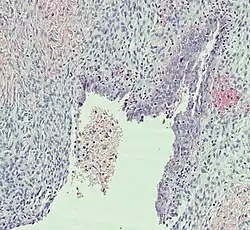

| Corpus luteum cyst |

|

| |